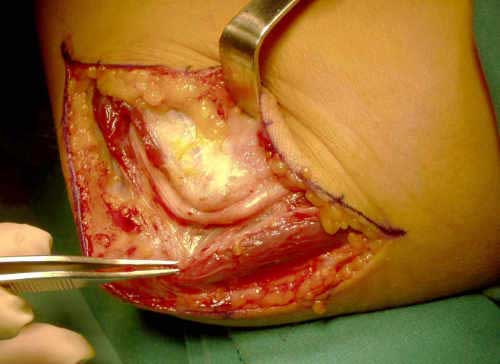

Nuestra actitud personal es realizar inicialmente una liberación in situ, que consiste en la descompresión del nervio en su recorrido alrededor del codo, valorando siempre la patología que nos podemos encontrar en el acto quirúrgico.

Es importante comprobar una vez liberado el nervio que no se subluxa. (Fig. 5).

Fig. 3: Incisión Quirúrgica

Fig. 5: Comprobación en flexión de la ausencia de subluxación del nervio